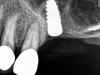

The implant is then delivered and should be well stabilized in the bone. If there is any mobility of the implant, it can either be placed a little deeper (if there is enough native bone) or the implant can be removed and the procedure aborted, in which case it would be a two-stage procedure. This should rarely occur with the tapered designed implant, even with only 2 mm of native bone. Using a bone-level platform-shifting implant (or a tissue-level designed implant) is critical, as the hard and soft tissue will establish a biologic width. If an external hex type of implant is used and the shoulder is placed at the bone level, an expected bone loss of 1.5 mm to 2 mm will occur.24 Figure 10 shows proper bone-level implant depth placement with a platform-shifting design. In this case, a 3-mm healing abutment was placed at the time of surgery to avoid a secondary uncovering surgery, but an implant-level healing abutment could have been placed instead. As can be seen, there was only about 2 mm to 3 mm of native bone height. The membrane was raised about 8 mm to 9 mm. Comparing the radiograph on the day of surgery (Figure 10) to the 6-month postoperative radiograph (Figure 11) shows no loss of native bone, as well as the positive change in appearance of the grafted bone. The 3.5-month CBCT scan (Figure 12) shows good healing of the bone with no coronal bone loss. With minimal native bone present, as in this case, the use of a non-platform-shifting or non-tissue-level implant design could be problematic. After 1.5 mm to 2 mm of crestal bone loss, an external hex designed implant could develop instability with possible implant failure. If a non-tapered implant is used and bone loss occurs during healing, migration of the implant into the sinus could potentially occur. The surgeon can use either a healing abutment or implant-level closure screw over the implant shoulder. With patients who tend to use their tongues to explore or play with the area, or if the area is under a removable partial denture, a closure screw is recommended.

A 74-year-old man presented with only about 2 mm to 3 mm of native bone below the sinus in the No. 14 position (Figure 13). The composite graft used was an approximately 50:50 mixture of DFDBA (Bio-Oss®, Geistlich Biomaterials, www.bio-oss.com) with the addition of about 40% calcium sulfate by volume (Figure 14). The implant placed (Figure 15) was a 10-mm long, rough-surfaced, platform-shifting implant (tapered 4.2 mm to 2.8 mm), and the sinus was raised about 8 mm. The postoperative radiograph taken at 4 months (Figure 16) showed some shrinkage of the graft, but no demarcation of the old sinus floor in the area.